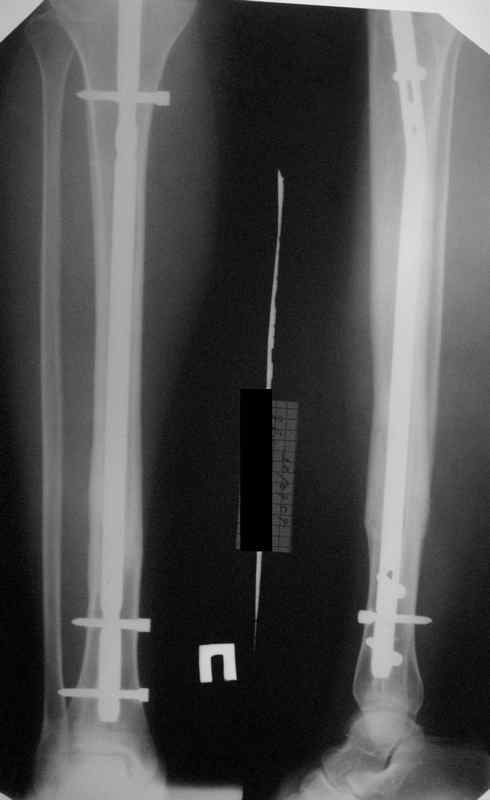

Re: неправильно фиксированный перелом

Большинство коллег высказалось против реостеосинтеза и представленные снимки этому подтверждение-данный кососпиральный перелом репонируется идеально только открыто,что при БИОС не так существенно.

Здесь проблема не в идеальности репозиции, а в запасе усталостной прочности. Срастаться там может небыстро, диастазы довольно большие.

И когда еще и отломок короткий, и отверстие совсем рядом, это может привести к перелому стержня. За последние годы у нас было несколько пациентов, оперированных в других учреждениях с

подобным положением отломков, с такими переломами гвздей. И сейчас переделать куда как проще и легче, чем иметь дело со сломанным гвоздем.

Антон, дорогой, важнее вальгуса тут близость верхнего отверстия к перелому и отсутствие уверенности в быстром сращении из-за большого

диастаза.